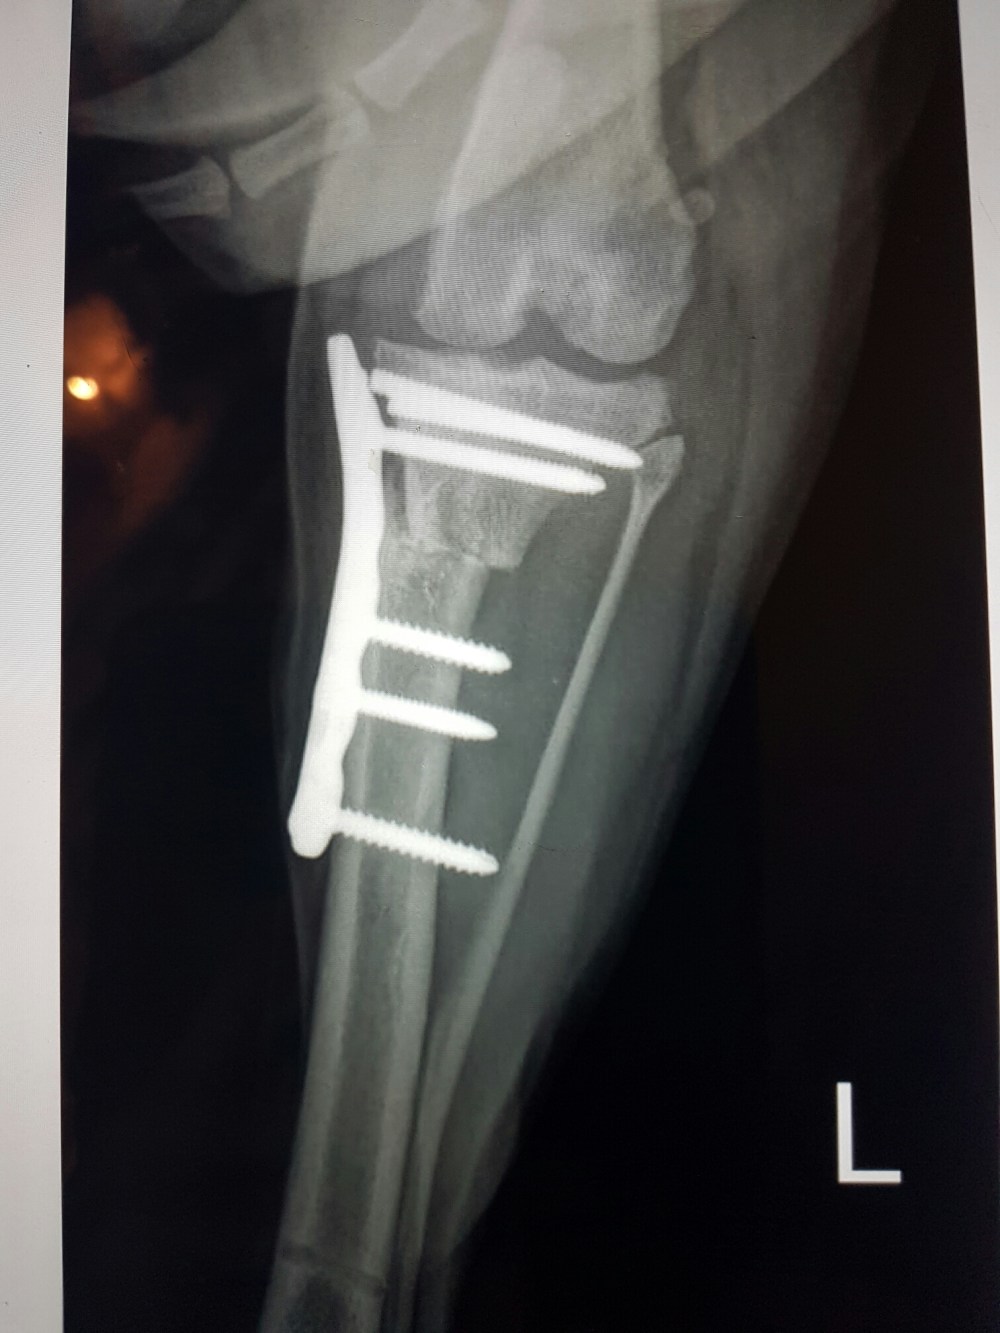

Han har fått gjort en TPLO – operasjon. Dvs at øverste del av leggbenet er saget over og satt på plass igjen i en litt annen vinkel slik at ikke korsbånd blir nødvendig. Herligheten blir så festet med en metallplate og seks skruer. Emil har gjort ettellerannet på den turen i hagen sånn at to skruer har løsnet og øverste del av leggbenet har fått seg en sprekk.. Det vil si at det hele er litt lealaust og at han i praksis går med et åpent brudd.